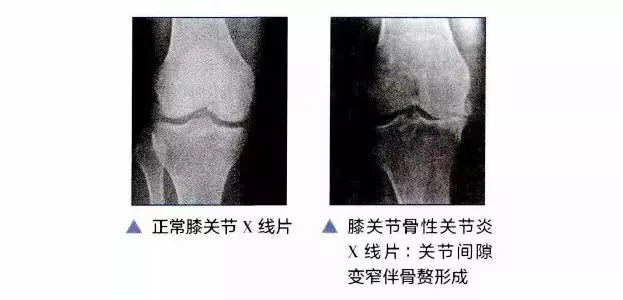

您是否经历过膝盖疼痛无法行走?是否稍微动动就听到膝关节沙沙沙的响声?这些问题困扰您很久,却不知道是不是真的有问题,下面小编带您了解一下您的膝关节。

看膝关节有无肿胀,有无左右膝关节不对称,前者说明可能有滑膜炎症、关节积液。后者说明可能有大腿肌肉的萎缩,这些都是膝关节骨性关节炎的常见发病原因。

按压髌骨及活动膝关节,如果按下去有酸痛或者感觉到有关节内软骨摩擦的沙沙的声音,提示膝关节的髌骨可能出现问题。

指的是特定的关节活动,如果关节一活动就疼,那么大部分人都知道关节出问题了。但是如果这时候才就诊,往往病情比较重了。我们说的动,是指进行某一个特定的活动,如上下楼梯时就疼,那么应该警惕。上下楼悌疼痛是早期膝关节骨性关节炎的表现之一,如果没有早期干预,后面发展到走平路甚至晚上睡觉都痛,那么治疗起来也病程也相对较长了。